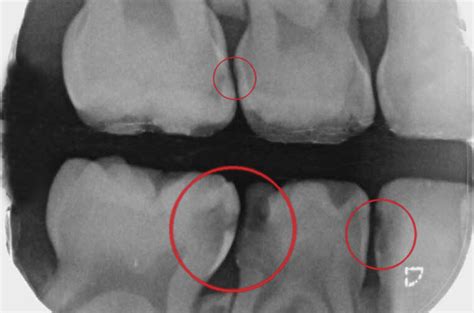

Diagnóstico de las caries interproximales

Los rayos X dentales son la técnica principal para diagnosticar caries interproximales. En las radiografías, una caries interproximal se verá como una sombra en el espacio entre los dientes. La prueba diagnóstica más adecuada para las caries interproximales será una radiografía oral y una exhaustiva exploración dental.